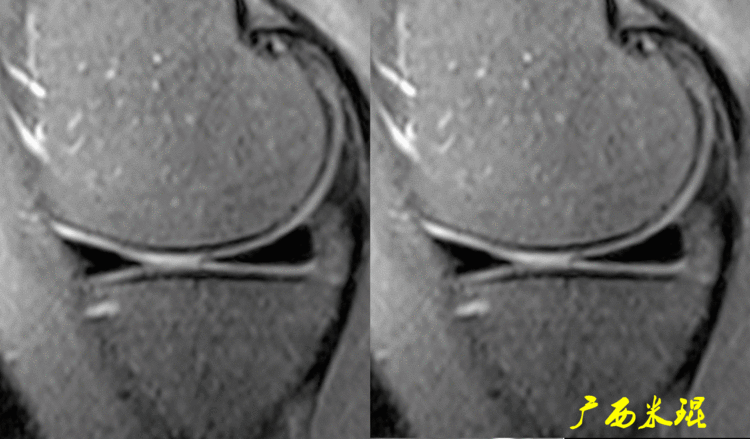

一、半月板损伤MR诊断的思路1、单纯就半月板改变诊断半月板损伤半月板信号(3级信号)及形态的异常是诊断半月板损伤最为直接的征象,当我们在阅片当中发现这些征象,一般情况下都能够确诊半月板损伤,下面这张MR,我们发现外侧半月板后角出现3级信号,所以能够确定其半月板损伤。

2、从发病机制诊断半月板损伤并不是每个病人都能够这么清晰的显示半月板的信号改变,同样这张MR,我们发现患者出现明显的对吻征,対吻征是诊断ACL损伤的重要体征,说明病人受伤的同时膝关节扭转严重,甚至出现轴移,这种情况下(损伤/发病机制)外侧半月板后根极其容易受伤,我们再认真的阅看其他截面,就很容易找到半月板损伤的佐证。